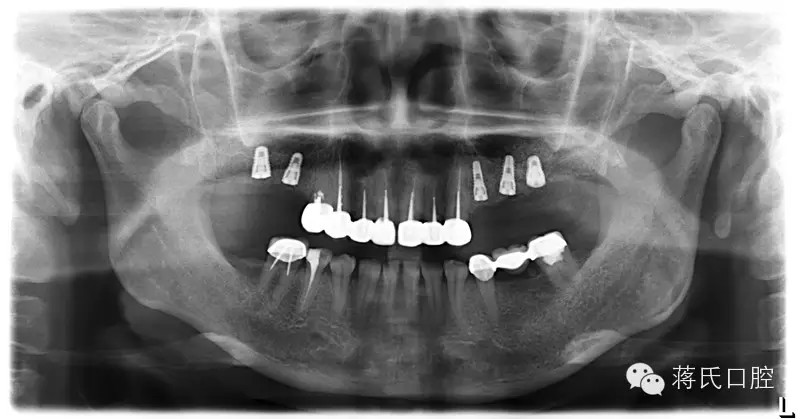

種植前X線(xiàn),左側(cè)外提升右側(cè)內(nèi)提升